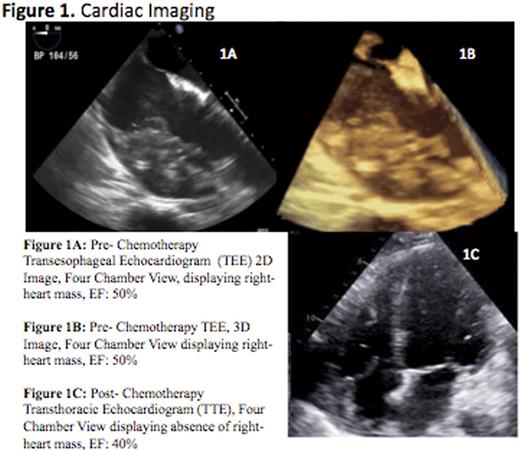

Subsequent work up included a cardiac MRI, which displayed a dense 7.5 cm by 3.5 cm mass involving the right ventricle and right atrium, wrapping around the great vessels. Right heart cardiac catheterization with endomyocardial biopsy was performed which revealed clusters of large atypical B lymphoid cells with the following immunophenotype: CD30+, CD79a+, Pax5+, Alk 1-, CD138-, CD 10-, Bcl 2-, Bcl 6-, CD45-, focally CD20+, Ki67: 80-90% (Figure 2). These findings were consistent with diffuse large B cell lymphoma (DLBCL). His PET-CT demonstrated absence of extracardiac lesions, confirming the diagnosis of primary cardiac lymphoma (PCL) (Figure 3).